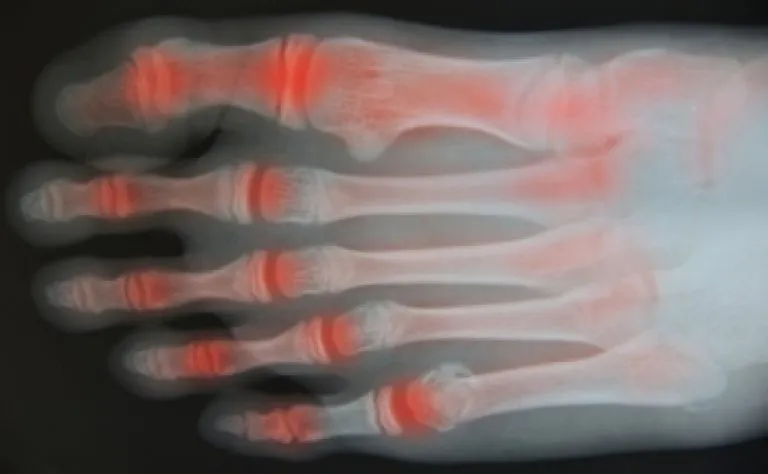

Plantar fasciitis often feels like a sharp, stabbing pain in the heel, particularly with the first steps in the morning or after prolonged rest periods. It can also cause a dull ache or burning sensation.